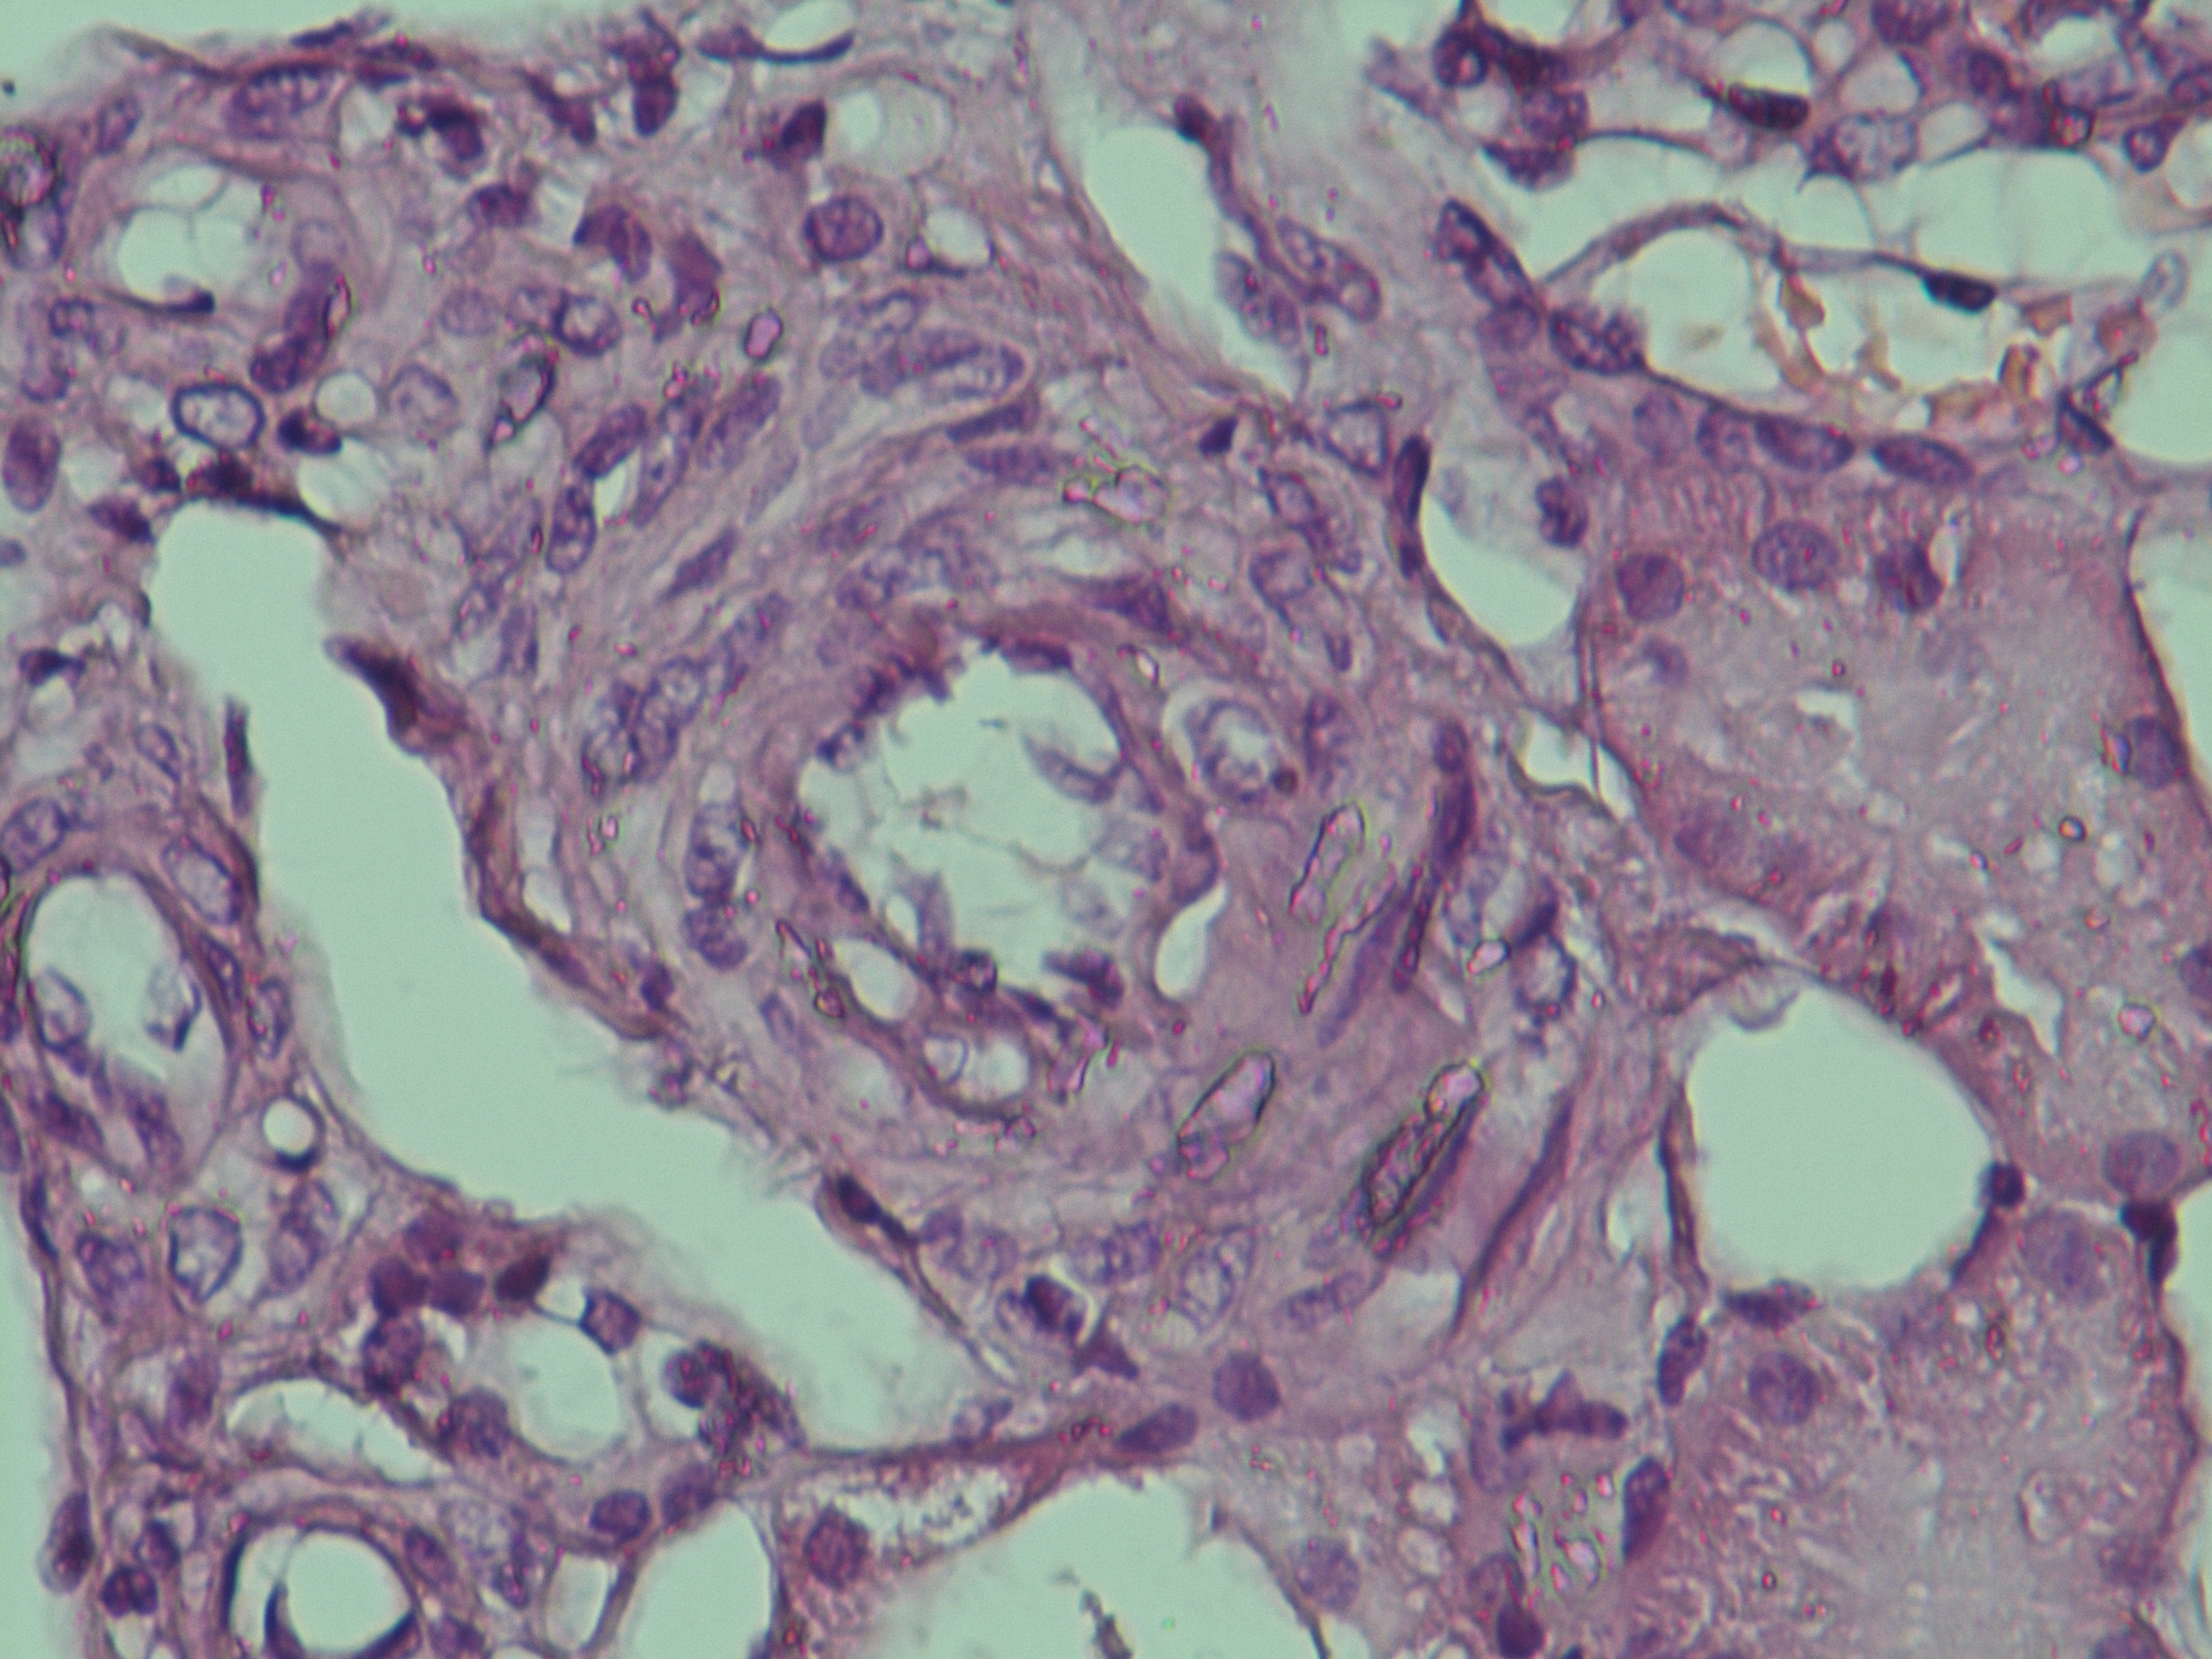

С целью определения гормональной активности образования был выполнен супрессивный тест с 1 мг дексаметазона: кортизол плазмы на следующее утро в 08:00 – 4,03 мкг/дл (норма <1,8 мкг/дл), АКТГ – 0,55 пмоль/л (1,6–13,9 пмоль/л), метанефрин в суточной моче – 373 мкг/сут (норма <320 мкг/сут), норметанефрин в суточной моче – 464 мкг/сут (норма <390 мкг/сут). Биохимические показатели: глюкоза крови натощак – 6,8 ммоль/л, общий холестерин – 4,9 ммоль/л. С учетом незначительного повышения в суточной моче уровня метанефрина и норметанефрина на фоне большого размера образования (41 × 42 × 56 мм) феохромоцитома была исключена. Пациент был направлен в ФГБУ РНИОИ с диагнозом “адренокортикальный рак, глюкокортикоид-продуцирующий”. Была выполнена лапароскопическая адреналэктомия слева. Заключение гистологического исследования удаленного образования: “Морфологическая картина более всего соответствует феохромоцитоме, дискомплексированный вариант, с очагами некроза, кровоизлияний, инвазия стенки сосудов (рис. 2, 3). Результат иммуногистохимического исследования: S-100 – отрицательная реакция, Сhromogranin A – умеренно выраженная цитоплазматическая реакция в клетках опухоли, Synaptophysin – слабо выраженная цитоплазматическая реакция в клетках опухоли, Ki-67 – позитивная ядерная реакция в единичных клетках опухоли. Заключение: морфологическая картина и иммунофенотип более всего соответствуют феохромоцитоме”.

Рис. 3. Гистологическая картина удаленного образца надпочечника (окраска гематоксилином и эозином, ×120). Феохромоцитома злокачественная с умеренным инвазивным ростом в кору надпочечника (слева направо), сосуды, некрозы и перивазарная воспалительная инфильтрация.

После получения результата иммуногистохимического исследования было принято решение о получении “второго мнения”, для этого был проведен пересмотр материала в условиях НМИЦ эндокринологии: “В доставленном материале определяются фрагменты опухоли, представленной диффузными полями и трабекулярно-альвеолярными структурами. Опухолевые клетки среднего и крупного размера с обильной эозинофильной цитоплазмой и крупными полиморфными ядрами. Строма представлена тонкими и местами гиалинизированнымифиброваскулярными септами. Отмечается сосудистая инвазия и инвазия капсулы. Митотическая активность – 1 фигура митоза в 10 полях зрения при увеличении микроскопа ×400. Выполнено иммуногистохимическое исследование с антителами к MelanA, a-Inhibin, Chromogranin A, Ki-67; с Chromogranin A реакция выраженная диффузная, с остальными антителами негативная. Уровень пролиферативной активности по экспрессии Ki-67 менее 1%. Заключение: реакция и гистологические изменения соответствуют феохромоцитоме/параганглиоме с высоким риском метастазирования (7 баллов по шкале PASS, 3 балла по шкале GAPP). ICD-O code 8700/3”.